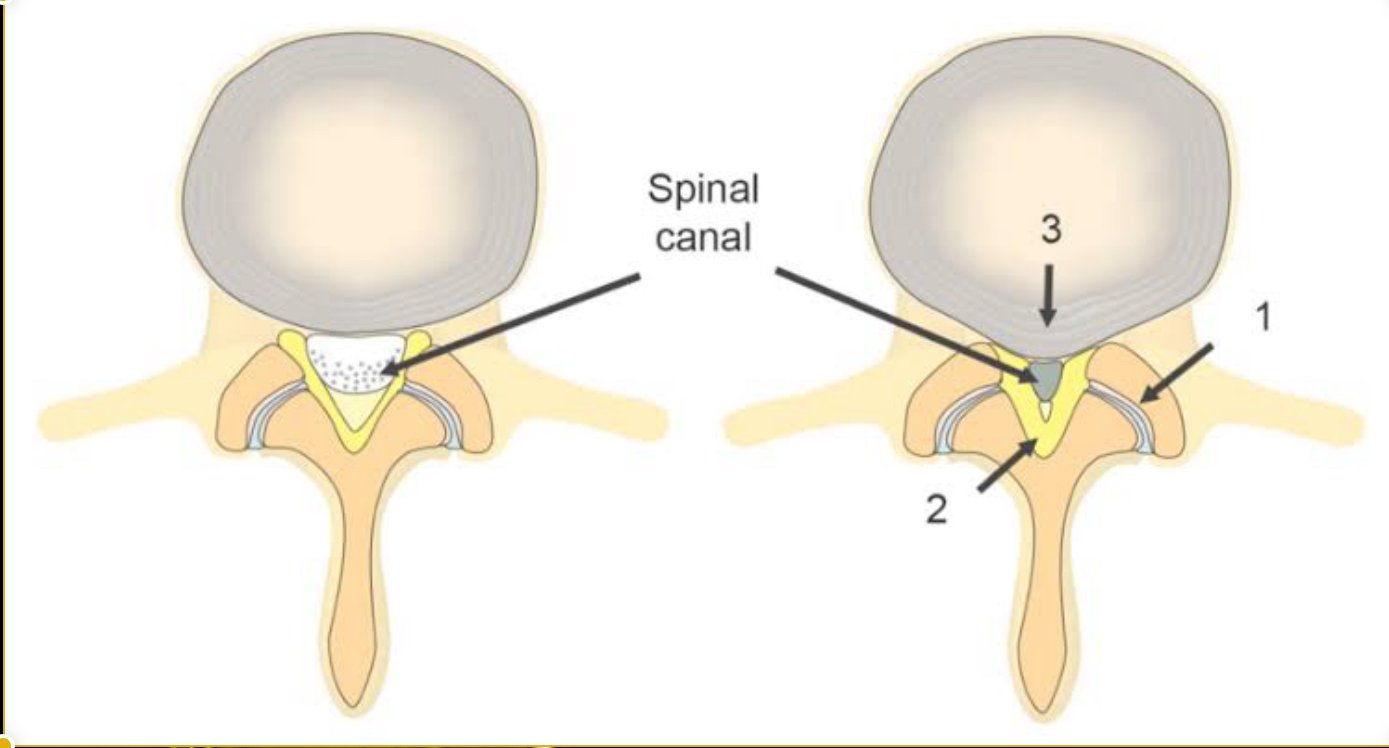

- Lumbar canal stenosis with instability

- Tubular retractors gently separate muscles (no cutting)

- Nerve compression is relieved

- The damaged disc is removed

- Pedicle screws and rods stabilize the spine